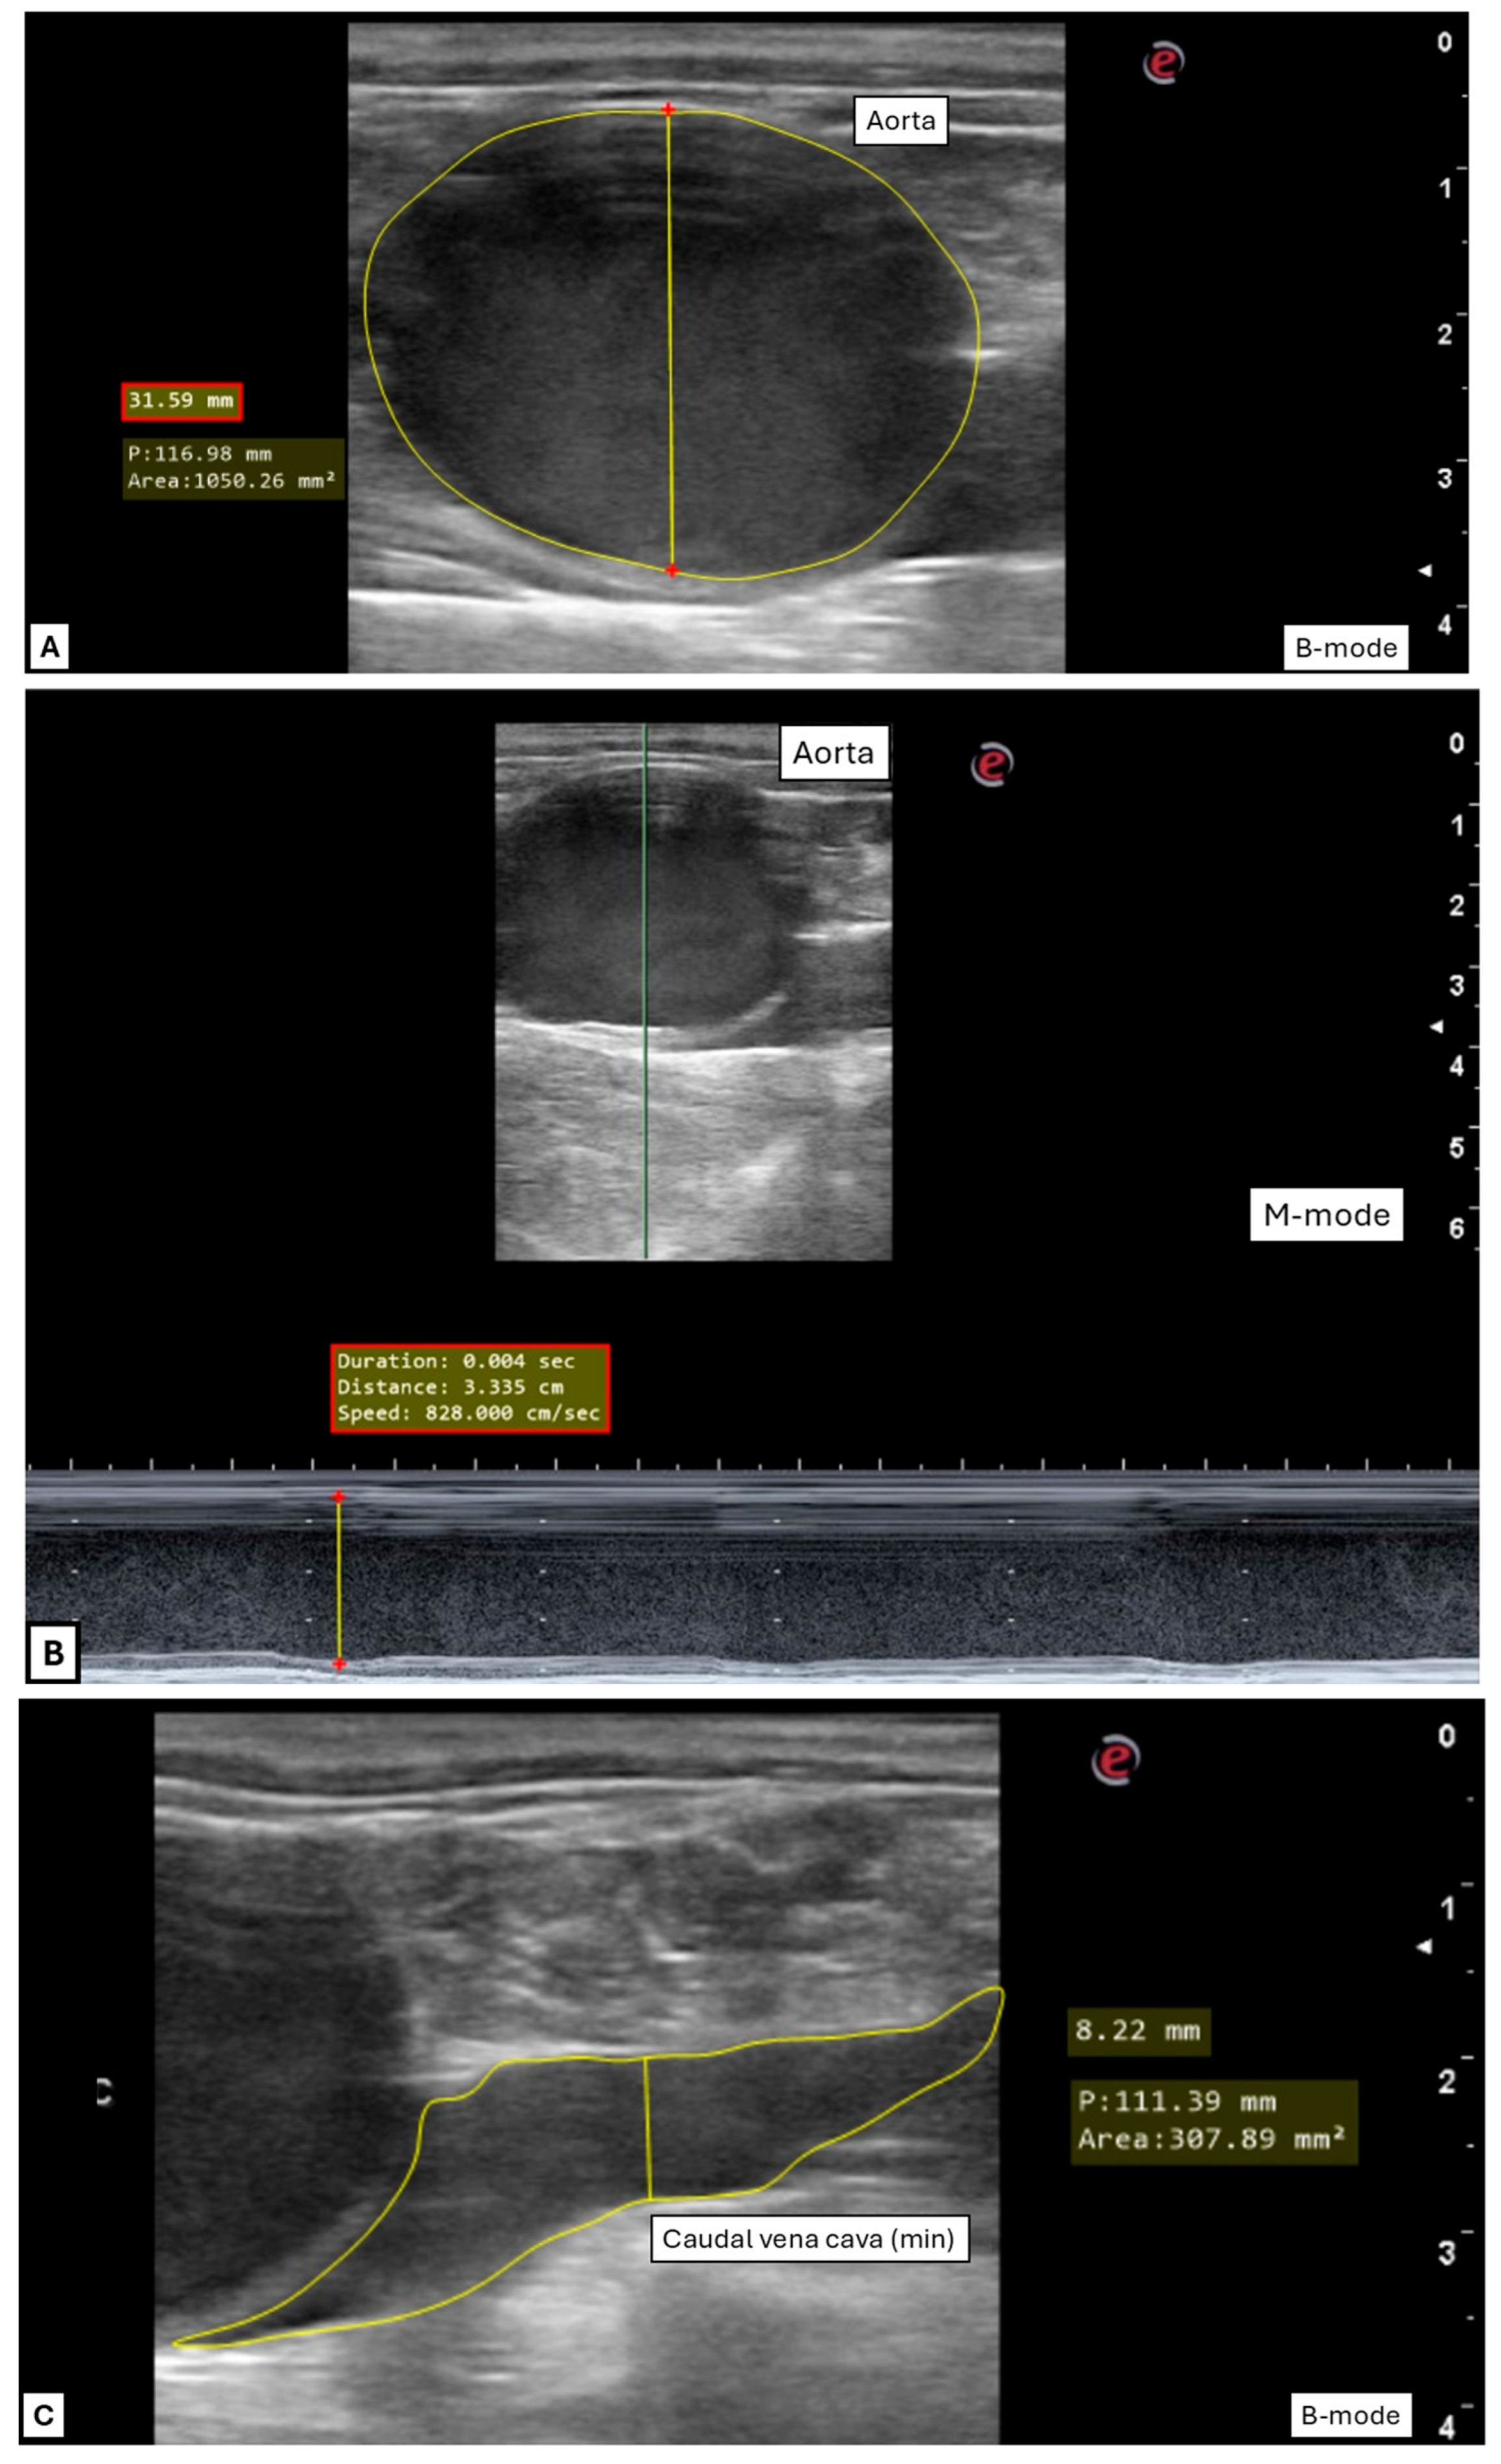

| B-Mode | M-Mode | |||

|---|---|---|---|---|

| Vessel | Mean ± SD | 95% Confidence Interval (Lower-Upper) | Mean ± SD | 95% CI (Lower-Upper) |

| Ao diam (cm) | 3.3 ± 0.3 | (3.23–3.40) | 3.3 ± 0.3 | (3.25–3.42) |

| Ao area (cm2) | 8.7 ± 1.7 | (8.27–9.14) | n/a | n/a |

| CVC diam min (cm) | 1.0 ± 0.3 | (0.91–1.07) | 1.0 ± 0.3 | (0.88–1.04) |

| CVC diam max (cm) | 1.4 ± 0.4 | (1.32–1.53) | 1.4 ± 0.4 | (1.34–1.54) |

| CVC area min (cm2) | 3.2 ± 1.2 | (2.86–3.46) | n/a | n/a |

| CVC area max (cm2) | 5.0 ± 1.7 | (4.56–5.43) | n/a | n/a |